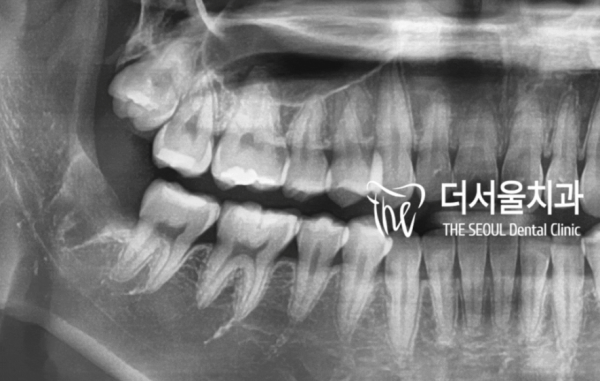

이 환자분의 엑스레이를 보면 옆 치아와 신경관이

거의 가까워서 고난이도의 수술로 볼 수 있습니다.

If you look at this patient's x-ray, the side teeth and neural tube

It's almost close, so you can see it as a high-level operation.